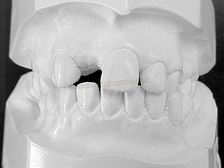

MODELOS DE ESTUDO EM GESSO (vista latera direita) |

MODELOS DE ESTUDO EM GESSO (vista latera esquerda) |

MODELOS DE ESTUDO EM GESSO (vista frontal) |